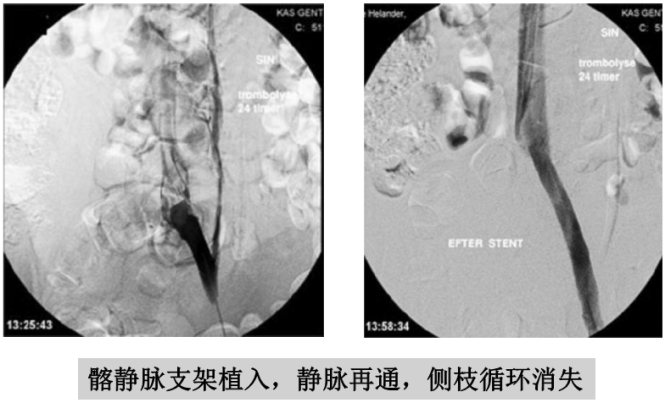

溶栓导管拔除前应做静脉造影,不仅可以判断溶栓效果,还可以发现和诊断髂静脉压迫综合征。髂静脉压迫综合征在正常人群中发生率约三分之一,在下肢深静脉血栓的病人中发生率较高。髂静脉压迫综合征一般发生在左侧,因为左侧髂静脉在生理上就位于右侧髂动脉和脊柱之间,很容易受压。这也是下肢深静脉血栓大多数发生在左侧下肢的原因。如果血栓没有完全溶解,且不准备接受髂静脉支架手术者,可以复查彩超后拔除导管。

出现髂静脉狭窄的深静脉血栓病人,如果不解除狭窄,近 期血栓完全溶解率较低,远期血栓复发率较高。所以,如果病 人经济条件许可,医院技术条件许可,在这种情况宜采取球囊 扩张、支架植入、手术修复等方法治疗。

手术的目的是减少深静脉血栓再次发生率,改善下肢静脉 回流,减少远期肢体水肿和溃烂的情况发生。一般在血栓溶解 后采取相关手术。

髂静脉狭窄在导管溶栓术中可以根据具体情况,酌情 做球囊扩张术,有一定作用。但是单纯球囊扩张后髂静脉容易 回缩,再次狭窄。

酌情考虑做髂静脉支架植入的病人有:(1)急性深静脉血栓病人,导管溶栓或切开取栓术后,髂静脉明显狭窄或闭塞,球囊扩张后残余狭窄超过 50%;(2)深静脉血栓远期形成较重的下肢肿胀溃疡,髂静脉狭窄或闭塞。